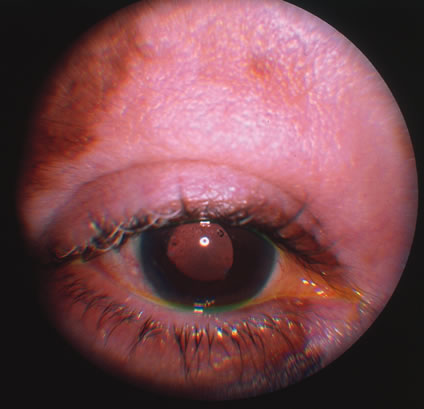

Kaposi's sarcoma is much more frequent in male homosexuals and bisexuals than in other patients with AIDS. Cutaneous lesions are usually red or violaceous, palpable, and nonblanching papules, nodules, or plaques, often appearing on the hard palate, nose, eyelid, and conjunctiva (Fig. 11). Visceral and lymph node involvement is common and often clinically silent. Biopsy specimens show proliferation of small, incompletely formed blood vessels lined by unusually large endothelial type cells, with extravasated red blood cells and infiltrates of spindle-shaped cells. Chemotherapy with etoposide, Vinca alkaloids, or interferon-α may be indicated in advanced cases.28

Fig. 11. The typical lesion of Kaposi's sarcoma on the conjunctiva.